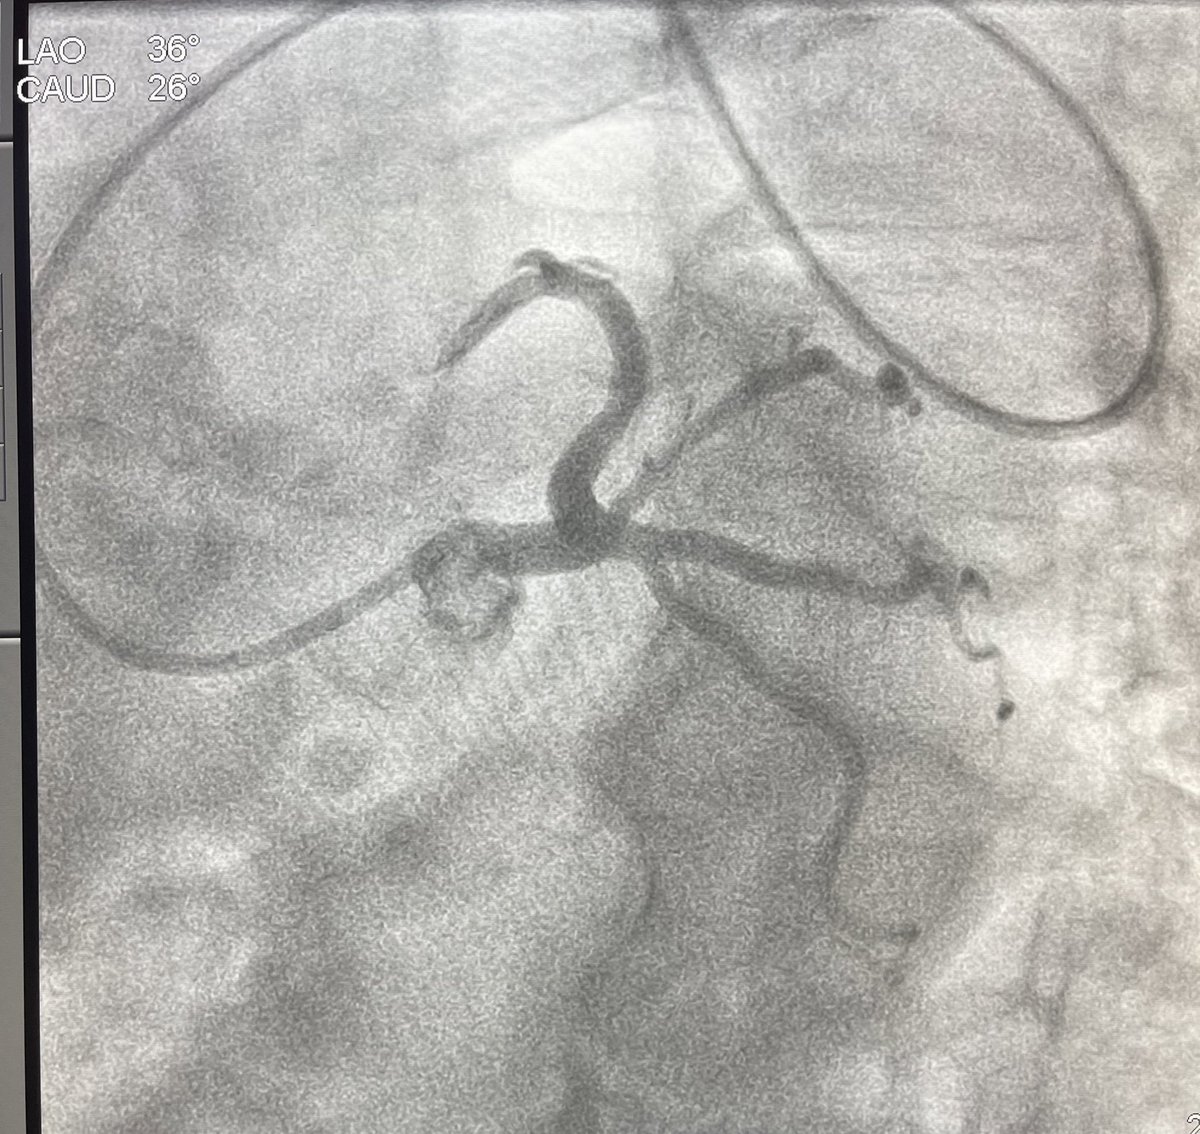

So proud of our team! Opened our second mTEER location today! @jgschwartzmd @AtriumSHVI @THillMD @SteveCl54400449 @MarkusSchererMD @SanjeevGulatiMD @garosemd